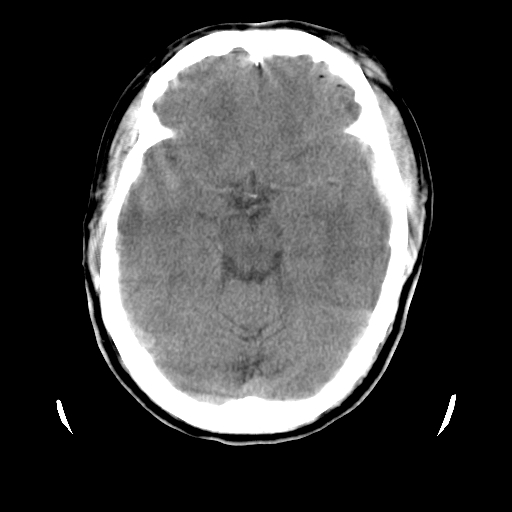

男,51岁,头外伤一小时,呕吐两次。

1)左侧中颅窝蝶骨翼后方硬膜外血肿。2)左侧颞顶部硬膜下血肿。3)蛛网膜下腔出血。4)左侧筛窦及双侧蝶窦炎症(或积血)。5)左侧额部头皮软组织肿胀。